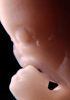

Carnegie Stage 19 (47 post-ovulatory days)

Most embryos at stage 19 are approximately 47-48 post-ovulatory days old and measure 17-20 mm in length. Distinguishing criteria for this stage include straightening of the trunk, the limbs extend nearly directly forward, toe rays are prominent, but interdigital notches have not yet appeared in the foot.

Although some of the photographs below show abnormal embryos, the animations and MRI slice images all depict normal embryos. Abnormal embryos are noted in the titles of the large photos when they are opened.